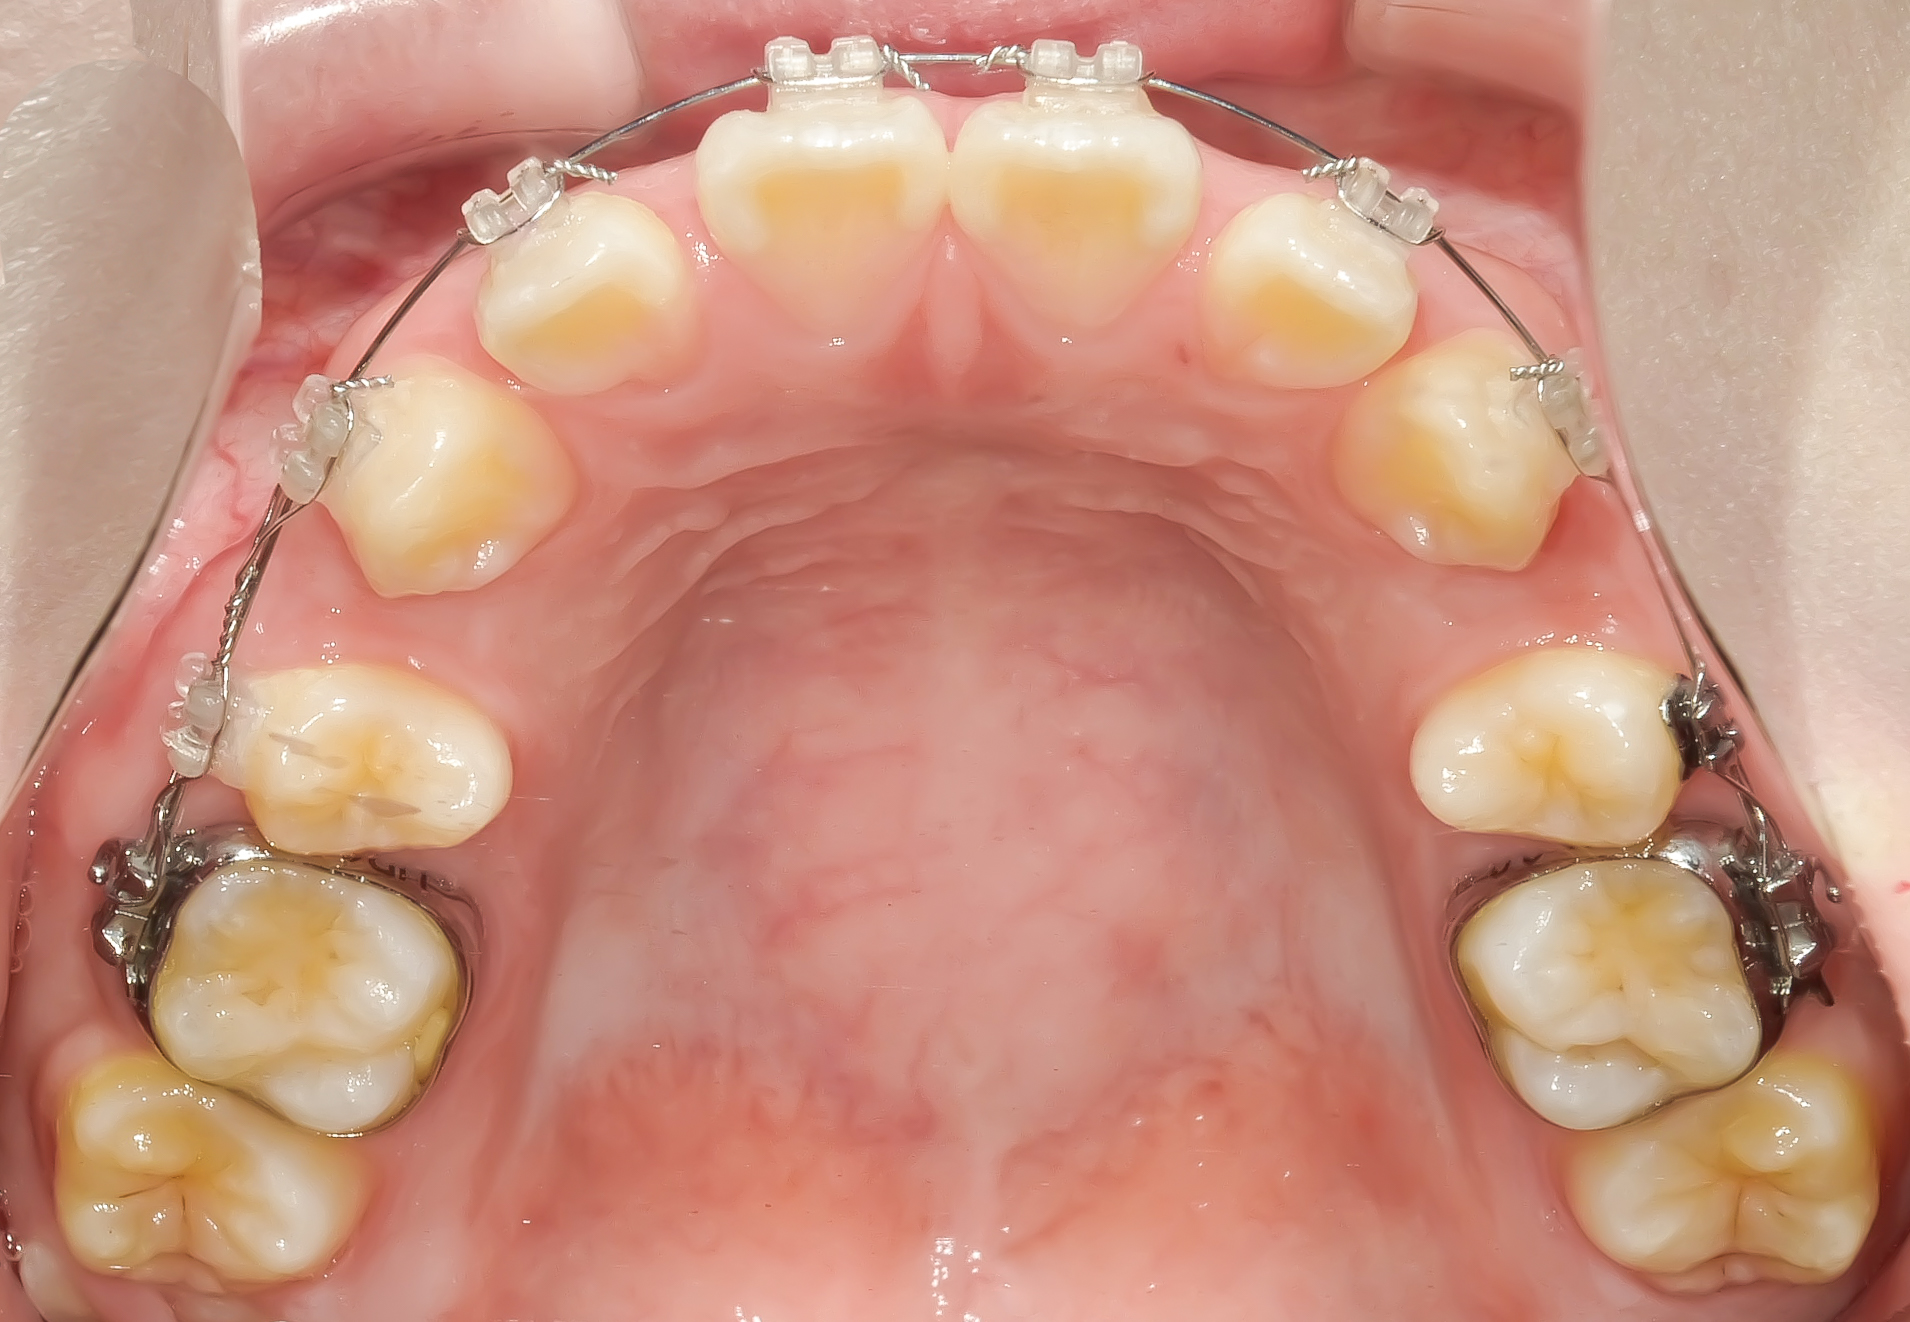

上顎に装置を装着した状態。

左右の前から4番目の歯を抜き、前歯を中に入れるスペースメイクを行います。

ワイヤーの超弾性(元の形に戻ろうとする力)が歯を並べます。